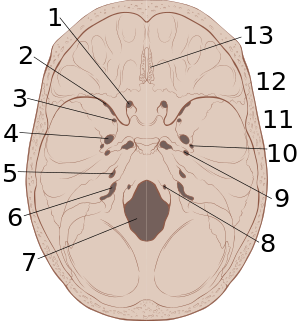

| نوع النزف | فوق الجافية | Subdural |

|---|---|---|

| المكان | Between the skull and the dura | Between the dura and the arachnoid |

| Involved vessel | Temperoparietal locus (most likely) - Middle meningeal artery Frontal locus - anterior ethmoidal artery Occipital locus - transverse or sigmoid sinuses Vertex locus - superior sagittal sinus |

Bridging veins |

| Symptoms | Lucid interval followed by unconsciousness | Gradually increasing headache and confusion |

| Appearance on CT | Biconvex lens | Crescent-shaped |